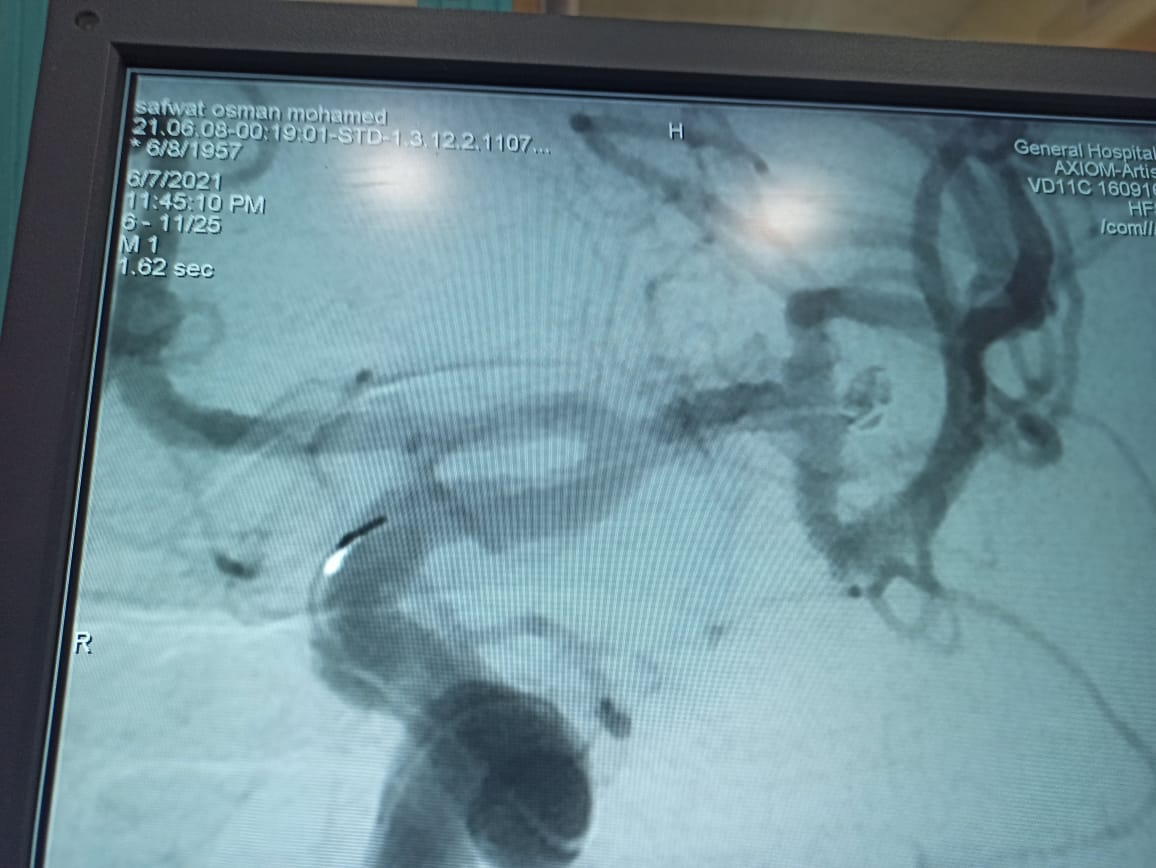

"الرعاية الصحية": نجاح أول قسطرة مخية لـ"مسن" تحت مظلة التأمين الصحي الشامل بالمجع الطبي بالإسماعيلية

أعلنت الهيئة العامة للرعاية الصحية، عن إجراء  قسطرة مخية ناجحة لمسن تحت مظلة التأمين الصحي الشامل لأول مرة، داخل المجمع الطبي بالإسماعيلية، يأتي ذلك استمرارًا لريادة الهيئة وحرصها الدائم على إجراء التدخلات الجراحية المستحدثة وبمنتهى الدقة لمنتفعي منظومة التامين الصحي الشامل بمحافظة الإسماعيلية.

وأوضح بيان الهيئة، اليوم، أنه تم عمل الفحوصات الطبية للمريض البالغ من العمر 63 عامًا، فور دخوله المجمع الطبي بالإسماعيلية، وتبين أنه يعاني من نزيف تحت الأم العنكبوتية ناتج عن تمدد شرياني بالمخ، وعليه تم إجراء القسطرة التشخيصية المخية للمريض، ووضع الخطة العلاجية له على يد الأستاذ الدكتور أحمد بسيوني، استشاري القسطرة المخية بمستشفيات الهيئة الرعاية الصحية والمشرف علي القسطرة المخية بالمجمع الطبي بالاسماعيلية .

وتابع البيان أن الهيئة تضم أفضل وأمهر الاستشاريين في كافة التخصصات الطبية، فيما ضم الفريق الطبي الذي قام بإجراء القسطرة المخية للمريض السالف ذكره ، الدكتورة مروة عرابي استشاري المخ و الأعصاب و القسطرة المخية و رئيس قسم المخ و الاعصاب و السكتة الدماغية، والدكتور  شريف الخطيب استشاري جراحة المخ و الاعصاب، والدكتور أحمد عيسى استشاري التخدير، وذلك تحت مظلة التأمين الصحي الشامل، ووفقًا لأحدث المعايير العالمية وبأعلى جودة بما لايحمل المرضى أي أعباء مالية أو مشقة الانتقال خارج محافظته للحصول على الخدمة الطبية اللائقة.

واستكمل بيان الهيئة، أن إجراء القسطرة المخية يمثل تتويجًا لجهود الهيئة العامة للرعاية الصحية لاستحداث حزم الخدمات وتقديم خدمات لم تكن موجودة داخل التأمين الصحي القديم، لافتًا إلى أن تكلفة العملية في القطاع الخاص تتراوح ما بين 50 و 400 ألف جنيه مصري، في حين يتم إجراؤها تحت مظلة التأمين الصحي الشامل بمساهمة لا تتعدى 300 جنيه.